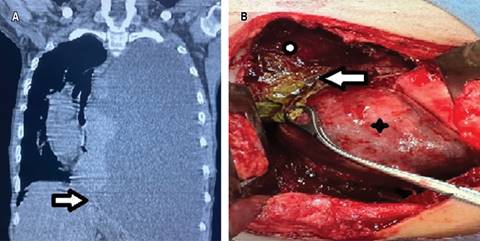

Caso clínico 2. Hombre de 27 años, en sus antecedentes destaca alcoholismo desde los 14 años y episodios de dolor abdominal presentados desde un año previo a la valoración, por lo que acude a atención hospitalaria. Refiere disnea progresiva además de aumento del dolor abdominal, a lo que se agrega dolor torácico. Se le realizó TAC de tórax que reportó ocupación de hemitórax izquierdo asociado a derrame pleural masivo, con desplazamiento a la derecha de estructuras mediastinales (Figura 2A). Se colocó sonda endopleural izquierda, la cual, tras la colocación, persiste con gasto de aproximadamente 600 mL diarios durante dos semanas, de aspecto oscuro de consistencia líquida. Continúa con deterioro respiratorio, por lo que es referido al Área de Cirugía de Tórax donde solicitan análisis del líquido pleural, el cual revela exudado hemático con niveles elevados de amilasa (195 U/L) y lipasa (3,095 U/L). Además, mostraba leucocitosis y trombocitosis en reporte de biometría hemática. Se complementa con TAC de abdomen y se identifica colección abdominal peripancreática que corresponde con pseudoquiste pancreático. Se decide pasar a quirófano; se realiza lavado y decorticación izquierda; se identifica derrame pleural secundario a pseudoquiste pancreático comunicado a hemitórax izquierdo a través del hiato esofágico, atrapamiento pulmonar, derrame pleural septado y fibrotórax izquierdo (Figura 2B). En el posoperatorio, los drenajes pleurales produjeron bajo gasto, de aspecto serohemático (30-100 mL/día); son retirados al día cinco y siete del posquirúrgico. Se realizó TAC de control donde persiste colección abdominal mínima. Posterior a valoración por el Servicio de Gastroenterología, se decide mantener conducta expectante. El paciente cursó con buena evolución posquirúrgica y fue dado de alta en el día 10 del posoperatorio. En seguimiento posquirúrgico, al mes y a los tres meses con radiografía simple de tórax y a los seis meses con TAC de tórax, no presenta evidencia de complicaciones.